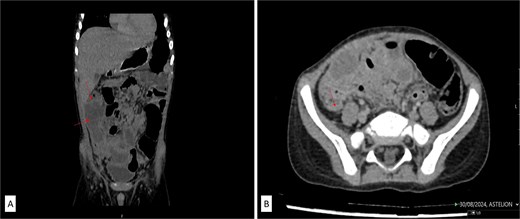

Histopathologic examination confirmed severe acute transmural appendicitis with thick fibrinopurulent deposits in one specimen (Fig. 2A and B) and secondary appendicitis with fibrinopurulent deposits on the serosa in the other (Fig. 2C and D). The patient had an uneventful postoperative recovery and was discharged in stable condition after 8 days. Intraoperative discovery of a duplicated vermiform appendix prompted a reevaluation of the preoperative CT scan, which revealed an additional appendix in a typical retrocecal position, measuring 24.1 mm in length, that was not initially detected (Fig. 3).

Postoperatively analyzed preoperative contrast-enhanced sagittal abdominal CT scan detected a retrocecal 24.1 mm long tubular structure (a smaller second secondary inflamed appendix) with a transverse diameter of 5.6 mm and a wall thickness of 1.8 mm adherent to/inseparable from the dorsal wall of the cecum (labeled).